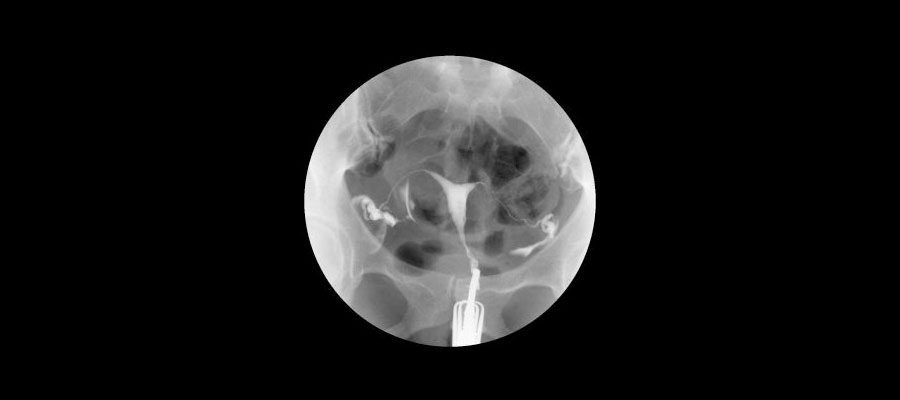

HSG normalde bir İngilizce ifadenin kısaltmasıdır ve tam olarak açılımı şu şekildedir: Histerosalpingografi. Bu çok karmaşık gibi görünen sözcüğü dilimize çevirdiğimizde ise tam olarak karşılığı ilaç ile çekilen rahim filmi anlamına gelmektedir.

Bu uygulama tahmin edilebileceği üzere jinekolog ya da daha bilinen bir tabir ile kadın doğum uzmanlarının uyguladığı bir işlem olup, rahimin içinin ve kadındaki vajina kısmında yer alan kanalların içine özel bir kontrast madde verilerek yapılan bir tanılama metodudur ve radyografik metotlar ile inceleme gerçekleşir.

Rahim filmi  sonuç olarak üstte ki bulgulardan da anlaşılacağı üzere özel bir uygulama ve özellikle hamile kalamayan kadınlar da tercih ediliyor. Zira bu yöntem sayesinde kadının neden hamile kalamadığı ve rahimin içi çok net bir biçimde görülebiliyor.

Tüplerin geçirgenliğini en iyi gösteren bir uygulama olduğu için böylesi bir sorun yaşayan kadınlarda adet kanamasının yani regl döneminin bitmesinden 3 ile 4 gün sonrasında yapılan bir uygulamadır.